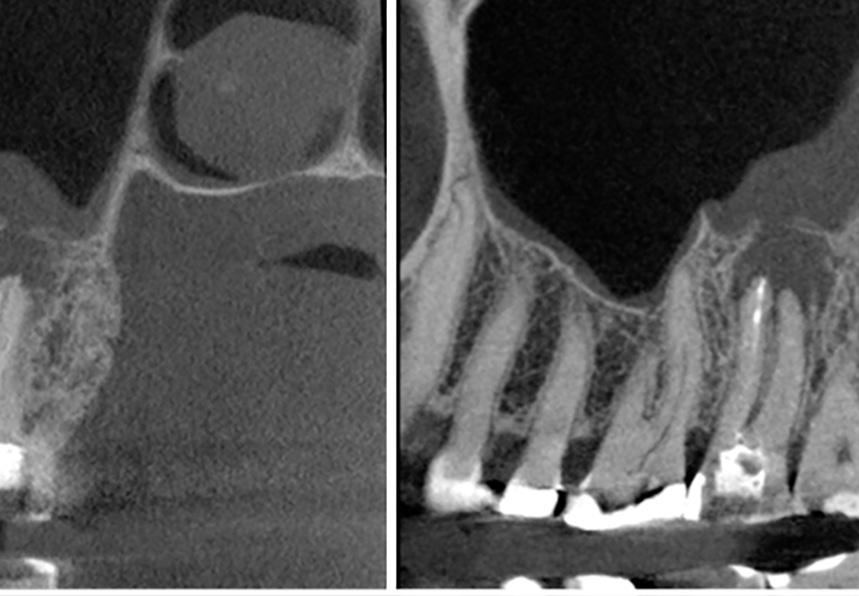

Enfoque regenerativo usando microcirugía endodóntica

Salvar los dientes afectados por defectos periapicales de grandes dimensiones

Cuando se trata de salvar los dientes, el éxito clínico depende en gran medida de los tratamientos periodontales y endo dónticos.1 De hecho, los dientes que se pierden durante el tratamiento perio dontal y los llamados «dientes insalva bles» suelen presentar problemas endo dónticos.

En los tratamientos endodónticos no quirúrgicos, los dentistas eliminan cui dadosamente la caries, la pulpa infla mada o infectada, limpian, desinfectan y conforman los conductos radiculares, y colocan una obturación para sellar el conducto. La tasa de éxito de este tra tamiento es menor cuando las lesiones

periapicales son extensas. En estos ca sos, el tratamiento endodóntico quirúr gico es una alternativa.

Las lesiones periapicales se encuentran entre las lesiones patológicas más comu nes en el hueso alveolar.2 Este tipo de le siones provoca defectos óseos y, cuando son grandes, el organismo no es capaz de regenerar hueso nuevo para rellenar los. Entonces el tejido conectivo invade el defecto óseo y afecta a los resultados clínicos.3

Injertar el defecto con un sustituto óseo y cubrirlo con una membrana reabsorbi ble puede ayudar al organismo a corregir

el defecto. En los tratamientos endodón ticos regenerativos para defectos gran des, como con la terapia periodontal regenerativa, los dentistas usan hueso autógeno y biomateriales, o una mezcla de ambos.

Los endodoncistas deberían diagnosti car la situación clínica, incluido el acceso al conducto, la ubicación y la anatomía de los dientes y de los tejidos circundan tes, y en caso de recidiva, la calidad del tratamiento endodóntico más reciente. Solo así es posible hacer un tratamien to no quirúrgico o quirúrgico apropiado.

Microcirugía periapical regene rativa

La microcirugía periapical regenerativa emplea los principios fundamentales de la endodoncia, la periodoncia y la odonto logía oral y restauradora. Por lo general, el objetivo del tratamiento es eliminar todos los posibles factores causantes de lesio nes periapicales, reparar la arquitectura del tejido periapical perdido y conservar la estructura y la anatomía de la raíz y de los tejidos blandos. También es importan te prevenir la recidiva de la enfermedad a largo plazo.

En lugar de extraer o sustituir los dientes con implantes dentales, los endodoncistas prefieren prolongar la funcio‑ nalidad de las piezas dentales con raíces con traumatismo. Los avances actuales en la tecnología, los procedimientos y los biomateriales, permiten a estos especialistas salvar los dientes con una increíble tasa de éxito.

| A Tomografía computarizada de haz cónico (CBCT) coronal o sagital que muestra la proximidad de la lesión periapical y el seno maxilar. | B Oclusión correcta antes del tratamiento. | C Plantilla quirúrgica 3D para guiar el acceso. | D Osteotomía con el Piezotome Cube (Acteon, EE. UU.) usando la punta SL1 después de elevar el colgajo. | D Osteotomía con el Piezotome Cube (Acteon, EE. UU.) usando la punta SL2 | F Preparación retrógrada sobre la raíz mesiovestibular con una punta Berutti (EMS, Suiza) e irrigación salina. | G Biocemento Bio C Repair (Angelus, Brasil) aplicado en el conducto mesiovestibular. | H Fotografía con el microespejo de 3 mm para comprobar la obturación retrógrada en la raíz distovestibular del segundo molar derecho superior. | I Geistlich Bio-Oss® Small 0,5 g. (Geistlich Pharma AG, Suiza) en el sitio quirúrgico. | J Cavidad quirúrgica rellenada con Geistlich Bio-Oss® Small. | K Membrana Geistlich Bio-Gide® 25 × 25 mm usada para cubrir el injerto. | L Radiografía final después de la cirugía.

17 A B C D E F J K L H I G

FIG. 1: Microcirugía periapical regenerativa para tratar la periodontitis apical alrededor de las raíces mesiovestibular y distovestibular del diente

La microcirugía periapical regenerativa incluye los siguientes pasos (figura 1):

1. Aumento mejorado para una resección mínima de la raíz;

2. Preparación ultrasónica del ápice de la raíz;

3. Obturación retrógrada con un mate rial biocerámico para la reparación de la raíz; y

4. Regeneración tisular guiada en el lu gar del defecto óseo.

Los índices del éxito de la microcirugía periapical regenerativa han aumentado de manera notable en los últimos años gracias a los avances en las técnicas di gitales para la planificación, la microsco pía, los instrumentos microquirúrgicos y los biomateriales para la regeneración ti sular guiada.3 4

Uso biomateriales para las microcirugías periapicales y, hasta la fecha, estoy muy satisfecho con los resultados clínicos. El protocolo me ha permitido ayudar a mu chos pacientes a conservar sus dientes naturales insalvables, y a mantenerlos sanos y funcionales. Recientemente, mis colegas y yo publicamos un caso clínico donde detallábamos el protocolo y el re sultado clínico en el manejo de una lesión radicular grande mediante microcirugía periapical regenerativa.3 El quiste medía 40 mm en la zona más grande, y afectaba a varios dientes anteriores, a ambas placas corticales y en parte al suelo nasal. Debi do a las grandes dimensiones del defecto, decidimos usar una mezcla de Geistlich Bio‑Oss® y hueso autógeno obtenido de la rama ascendente de la mandíbula, junto con fibrina rica en plaquetas. El resulta do clínico era satisfactorio 4 años después de la cirugía (es decir, en el momento de la publicación). Además, cuando estudia mos las imágenes de la tomografía com putarizada de haz cónico, observamos que los tejidos estaban bien integrados, había hueso cortical nuevo y una radio pacidad y una forma trabecular parecidas a las del hueso nativo adyacente.